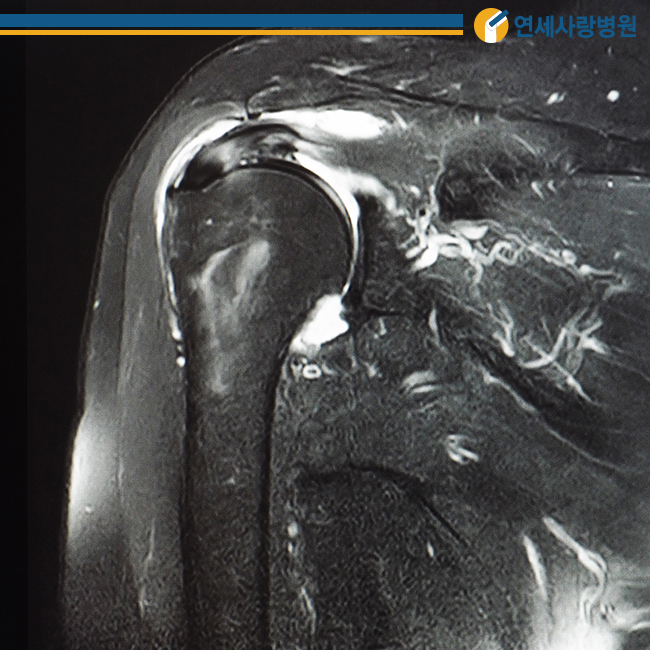

관절낭은 팔 위와 어깨 관절을 얇고 넓게 감싸 움직임을 부드럽게 하는데, 여러 원인으로 인해 염증이 생기면 관절낭 자체가 매우 두꺼워지고 힘줄이나 인대가 유착돼 딱딱해집니다. 이때 발생하는 통증을 오십견이라고 합니다.

50대 전후에 많이 발생한다고 해서 오십견이라고 불리고 있는데, 정확한 명칭은 동결견 혹은 유착성 관절낭염이라고 불립니다. 어깨를 움직이는 데 제한이 있을 뿐만 아니라 어깨 관절을 움직이려고 해도 더 이상 움직이지 않기 때문에 주의가 필요합니다.

오십견의 정확한 원인은 밝혀지지 않았습니다. 다만 노화로 인한 어깨 관절의 퇴행성 변화와 회전근개 파열 및 석회성 건염 등의 질환으로 인한 만성 통증, 어깨 주변 외상 등이 대표적인 원인으로 꼽힙니다. 이 경우 관절을 오랫동안 사용하지 않음으로써 주변 구조물과 유착돼 딱딱해지는 섬유화가 생겨 수동적인 움직임이 제한됩니다.